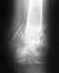

Проведено МКСТ-исследование грудного отдела позвоночника.

Грудной кифоз выпрямлен. Тело Th11 позвонка деформировано, неравномерно снижено по высоте, определяется оскольчатый перелом тела Th11 позвонка справа и в передних отделах, слева высота тела сечением в задних отделах до 22 мм, в передних отделах до 12 мм, справа мах осколок сечением до 28 на 14 мм, который в задних отделах тесно прилежит к правому реберно-позвоночному сочленению в его каудальных отделах, не деформируя его. На уровне Th11-12 имеется угловая деформация позвоночника до 159 градусов. Межпозвонковый диск на уровне Th11-12 неравномерно снижен по высоте, мах в передних отделах слева.

Высота тел других позвонков на уровне исследования сохранена. Тела других позвонков имеют обычную форму и размеры, костная структура не изменена. Замыкательные пластинки уплотнены. Имеются неравномерные сужения суставных щелей, субхондральный склероз, краевые сотеофиты. Кальцинированы жёлтые связки.

Существенных выпячиваний дисков не выявлено. Область невральных каналов без особенностей.

Сагиттальный размер позвоночного канала на уровне Th1-12-13-14 мм, на других уровнях 13.5-15 мм.